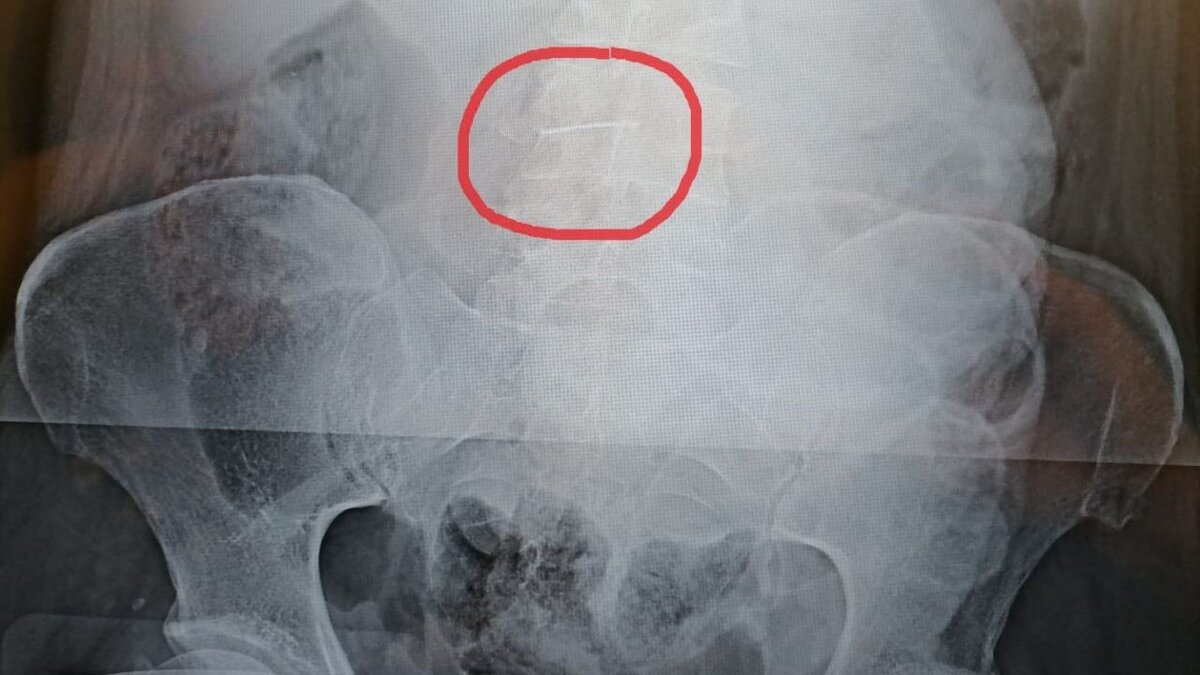

Как уточнили в облздраве, пациентку экстренно госпитализировали с подозрением на кровотечение в желудке или кишечнике, но этот диагноз не подтвердился. Зато рентгеновский снимок показал, что в животе у женщины… швейная игла.

Помимо иглы в брюшной полости, у пациентки была пневмония, что осложняло ситуацию. Тем не менее, хирурги успешно удалили инородный предмет длиной 5 см — игла такого размера чудом не повредила внутренние органы за много лет.